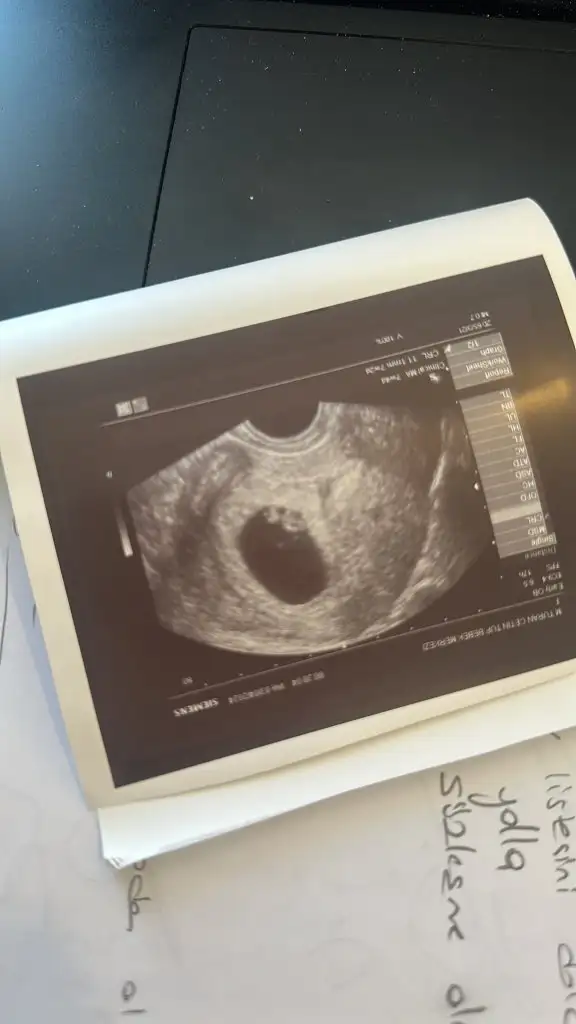

Siz anlıyorsunuz galiba banada yorum yapabilir mısınız bugün doktora gittim 12 haftalık ama küçük daha zamanı var dedi Meraktan catliyorumCanım erkek gibi

Canım kız gibi11+2 karından ultrason cinsiyet yorumu yapabilir mısınız ?

Canım kız gibiBanada bakarmisiniz 12 haftalik pek kıpırdamadan ama merak ediyorumEki Görüntüle 3420926 Eki Görüntüle 3420927 Eki Görüntüle 3420928

Canım erkek gibiBenimkinede bakarmısınız 12+2 haftalık ben kız olduğunu düşünüyorum ama bilemedim

Erkek gibi canım12 haftalık tam orda görünen ayağı var mı tahminde bulunmak isteyen ?